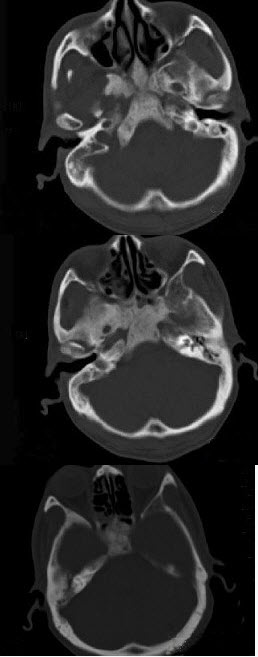

男性,56岁,鼻咽癌放疗后复查,CT扫描如图所示,请选择正确的答案()。

A、化脓性骨髓炎

B、骨结核

C、致密性骨炎

D、放疗后骨炎

E、骨瘤

D